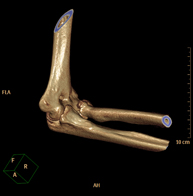

- TC Codo Exploración radiológica que mediante un sistema de rayos X y detectores que giran alrededor del paciente, reconstruyendo las imágenes por ordenador (TC Multidetector), permite el estudio de huesos, músculos y articulaciones del codo. Exploración radiológica que mediante un sistema de rayos X y detectores que giran alrededor del paciente, reconstruyendo las imágenes por ordenador (TC Multidetector), permite el estudio de huesos, músculos y articulaciones del codo.